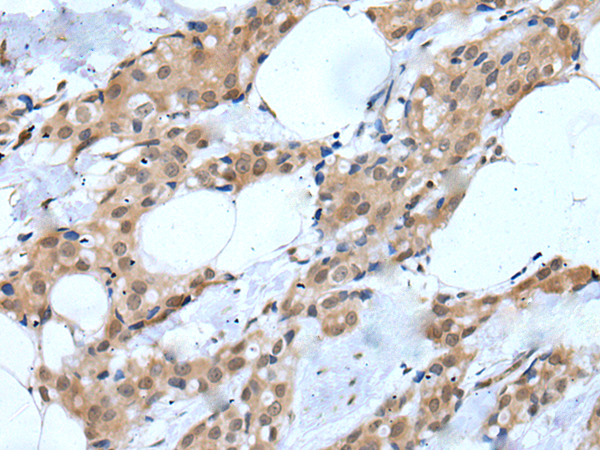

ELISA, IHC |

IHC positive control: |

Human esophagus cancer and human breast cancer |

IHC Recommend dilution: |

25-100 |